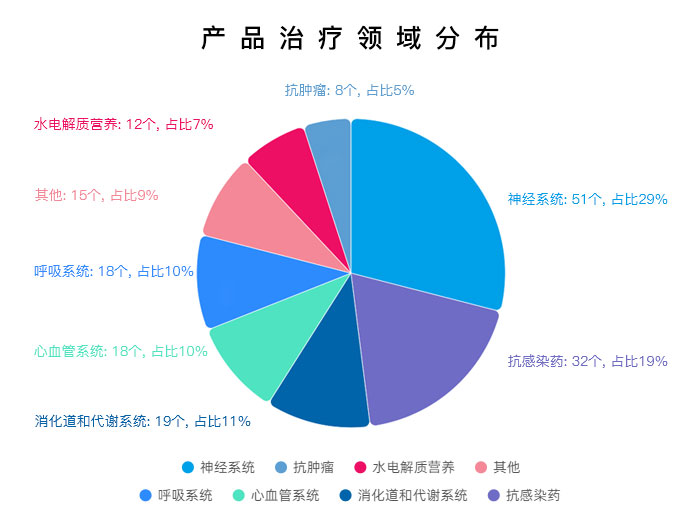

每年培育出百余项抗肿瘤、神经系统和心血管系统等治疗领域科研成果,以及多项国家级、省级重大科技创新产业化项目,2021年共开展化药研究项目共计163项。

所研品种主要涉及呼吸系统、神经精神系统、消化及代谢系统、抗感染、心血管系统、基础输液 (含透析、冲洗)等治疗领域

创新药开发管线

涉及肿瘤、自身免疫性疾病、脏器纤维化、麻醉镇痛、抗病毒药物等领域